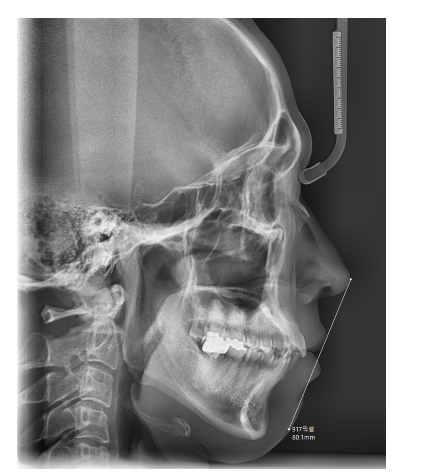

성인교정은 이미 성장판이 닫힌 상태에서 진행되기 때문에

치아 이동을 중심으로 교정을 하게됩니다.

때문에 주걱턱이나 무턱같이

턱 모양 자체를 개선하기 위해서는 "수술"이 필요하죠~

241118 턱 모양 자체를 바꾸지는 못하는 성인교정!!

반면에 소아 교정은..?

소아교정은 대개 6~12세 사이에 진행됩니다.

턱의 성장이 활발하게 이루어지는 시점입니다.

턱이 좁거나 부정교합이 예상되는 경우

턱 성장을 조절하면서 정상적인 교합을 유도해요~